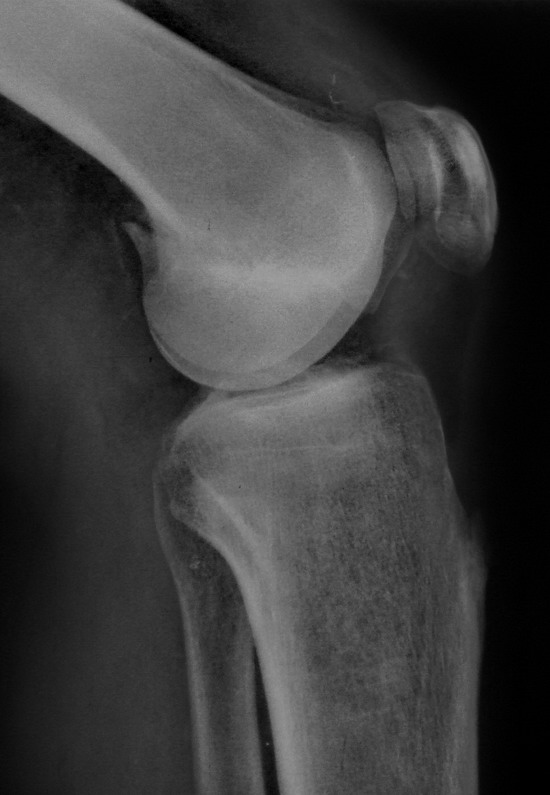

[Ortho] Нелеченный перелом Hoffa

Остеосинтез LCP пластиной